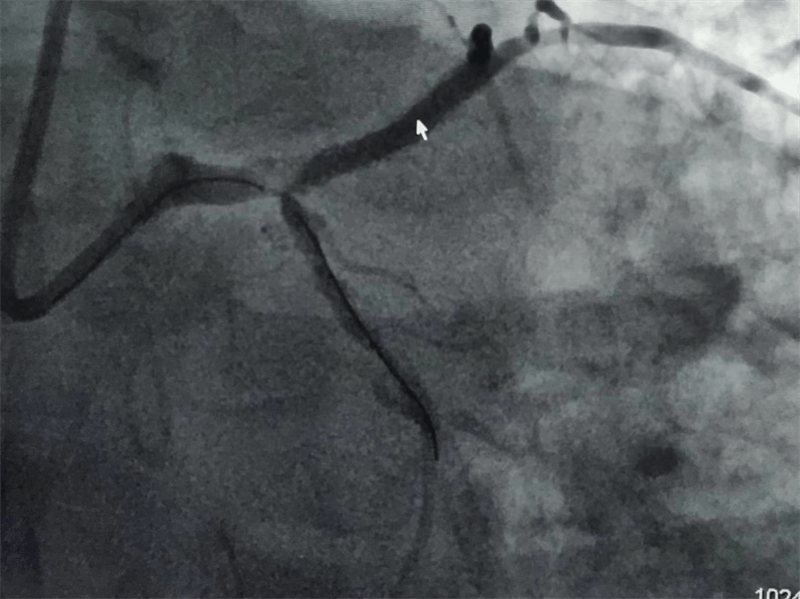

我們結(jié)合患者病變特點(diǎn),對(duì)回旋支支架內(nèi)閉塞病變處藥物球囊治療,左主干病變植入1枚支架,術(shù)后,造影顯示左主干病變處支架植入狀態(tài)良好,血管內(nèi)超聲顯示支架貼壁良好,患者血壓、心率穩(wěn)定,癥狀完全緩解,并安全返回重癥監(jiān)護(hù)室進(jìn)一步治療,術(shù)后張大伯無(wú)明顯不適,生命體征穩(wěn)定,病情明顯好轉(zhuǎn)。